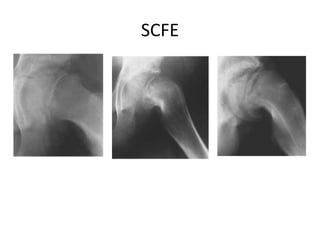

SCFE

• #43 Radiographic appearance of slipped capital femoral epiphysis (SCFE) on presentation. A, Appearance of acute SCFE on a frog-leg lateral view. The displacement of the epiphysis is suggestive of a Salter-Harris type I fracture of the upper femoral physis. There are no secondary adaptive changes noted in the femoral neck. B, Frog-leg lateral radiographs in a patient with many months of thigh discomfort and a chronic slipped epiphysis. Adaptive changes in the femoral neck predominate, and the epiphysis is centered on the adapted femoral neck. C, Frog-leg lateral radiographs of a patient with acute-on-chronic SCFE. The patient had several months of vague thigh pain, with sudden, severe exacerbation of that pain. The acute displacement of the epiphysis is evident. Unlike in acute SCFE (see A), secondary adaptive remodeling changes are also present in the femoral neck, beyond which the epiphysis has acutely displaced.